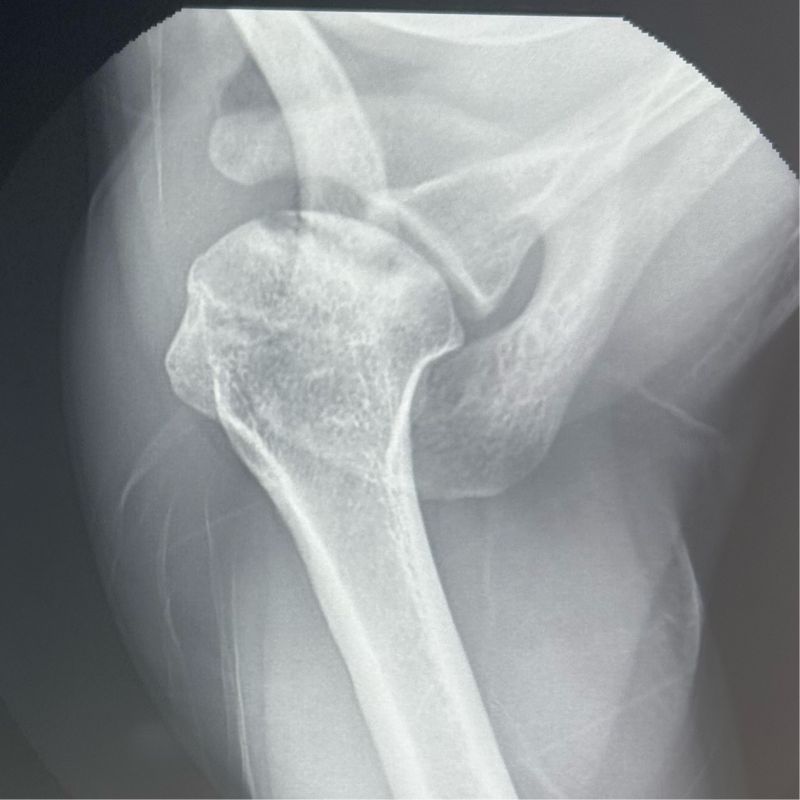

Reverse Shoulder Replacement

Had discussions on Arthroscopic Transosseous Repair, Reverse Shoulder Replacement, and Lower Trapezius Transfers. Explained our protocols and shared experiences. Had an engaging three days in our unit.

#Reverse Shoulder Replacement